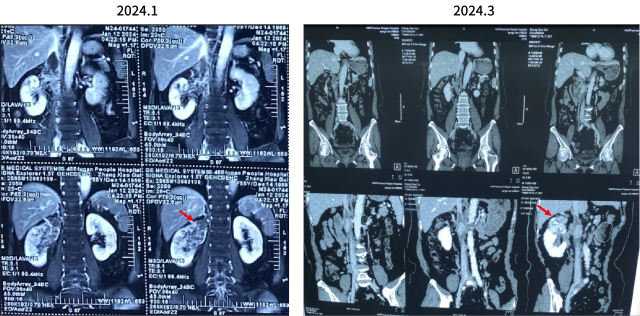

2022.1 靶免联合新辅助治疗

新辅助治疗前

新辅助治疗后

治疗后复查 CT(2022.7):左肾透明细胞 CA 治疗后改变,肿块较前缩小,强化程度减低,左侧副肾动脉可见;余况同前。

围手术期治疗

2022.7.11 行腹腔镜下左肾部分切除术。

术后病理:透明细胞肾细胞癌,ISUP 分级 G2 级,未见脉管内癌栓及神经周侵犯。